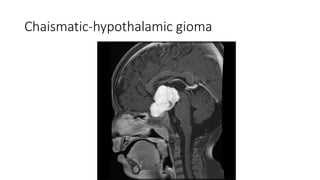

• Chaismatic-hypothalamic glioma

Chaismatic-hypothalamic gioma

Differential diagnosis • PapillaryCraniopharyngeoma • Chaismatic-hypothalamic glioma

Differtiating points Suprasellarmeninigioma Papillary Craniophayngioma Chaismatic Hypothalamic glioma Definition A tumour originating from arachnoid cell rest(which are related to dura mater arachnoid granulations) A benign mostly solid suprasellar tumor arising from squamous epithelial remnants of rathke’s pouch An astrocytic tumor Age Middle decades Middle decades Usually 4rth to 6th decade Childhood Location and extention Tebercular , dorsal or diapgragm sellae Often shows forward extension along dura mater of anterior cranial fossa Commonly located within the suprasellar region A purely intrasellar location is uncommon optic chiasm and optic tract. Chaismal tumor tumors may into hypothalamus

Differentiatig points Suprasellarmeningioma Papiilary Craniopharyngioma Chiasmatic Hypothamic glioma NECT Usullally broad dural based, hyperdense lesion Calcification is seen 20% cases Usuully solid suprasellar tumour Small cysts but not a significant feature calcification is absent Often large and lobulated when at chiasm and can extend into hypothalamus No calcification CECT/MRC+ Avidly homogenous enhancement Soild component-intense contrast inhencement Variable inhancement T2WI Frequently isointense to cortex High signal intesity High signal intensity Bony hyperostosis Usually present Absent Absent Dural tail sign Usually present Absent Absent